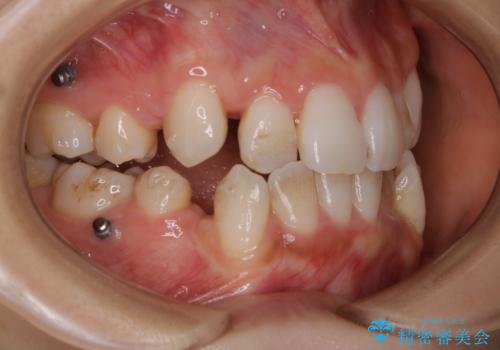

- インビザラインでのマウスピース矯正中に着色が気になるとのことでした。着色が全体的に付着していたためPMTC60分コースを行いました。

PMTC(保険外治療)は、毎日の歯磨きで落としきれない汚れや、コーヒ、紅茶・タバコのヤニなどの着色も除去します。目には見えない歯と歯の間・歯肉の境目・インビザライン中はアタッチメント周囲などに残っているプラーク(歯垢)もしっかり取り除きます。PMTCでは専門的な機械や材料を使用して、徹底的に汚れを除去するため、虫歯・歯周病・口臭予防などにつながります。